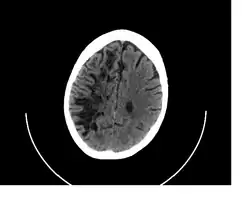

![]() A perivascular space as seen on CT | |

A perivascular space, also known as a Virchow–Robin space, is a fluid-filled space surrounding certain blood vessels in several organs, including the brain,[1] potentially having an immunological function, but more broadly a dispersive role for neural and blood-derived messengers.[2] The brain pia mater is reflected from the surface of the brain onto the surface of blood vessels in the subarachnoid space. In the brain, perivascular cuffs are regions of leukocyte aggregation in the perivascular spaces, usually found in patients with viral encephalitis.

In humans, perivascular spaces surround arteries and veins can usually be seen as areas of dilatation on MRI images. While many normal brains will show a few dilated spaces, an increase in these spaces may correlate with the incidence of several neurodegenerative diseases, making the spaces a topic of research.[4]

Perivascular spaces may be enlarged to a diameter of five millimeters in healthy humans and do not imply disease. When enlarged, they can disrupt the function of the brain regions into which they project.[5] Dilation can occur on one or both sides of the brain.[7]

Perivascular spaces are most commonly located in the basal ganglia and white matter of the cerebrum, and along the optic tract.[13] The ideal method used to visualize perivascular spaces is T2-weighted MRI. The MR images of other neurological disorders can be similar to those of the dilated spaces. These disorders are:[7]

Perivascular spaces are distinguished on an MRI by several key features. The spaces appear as distinct round or oval entities with a signal intensity visually equivalent to that of cerebrospinal fluid in the subarachnoid space.[7][14][15] In addition, a perivascular space has no mass effect and is located along the blood vessel around which it forms.[14]